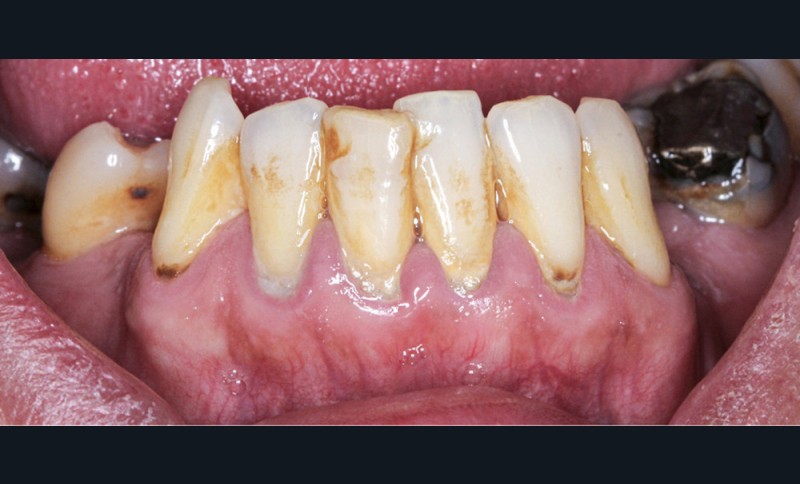

L’obésité, définie par un indice de masse corporelle (IMC) ≥ 30 kg/m2, est une maladie inflammatoire chronique complexe et multifactorielle caractérisée par un dépôt excessif de graisse dans le tissu adipeux. Selon l’OMS, depuis 1975, le nombre de cas d’obésité a presque triplé à l’échelle planétaire [1]. En 2020, près d’un Français sur deux était en surpoids, tandis que 17 % étaient obèses [2]. Or l’obésité est responsable d’une haute mortalité à l’échelle mondiale et est un facteur de risque majeur pour de nombreuses maladies, dont les maladies cardiovasculaires, le diabète de type 2 et certains cancers [1]. Son impact sur la santé des populations et son coût économique et social sont donc considérables. Ces deux dernières décennies, de nombreuses études ont montré que l’obésité pouvait aussi être incriminée dans la détérioration de la santé bucco-dentaire [3] (fig. 1 à 7).